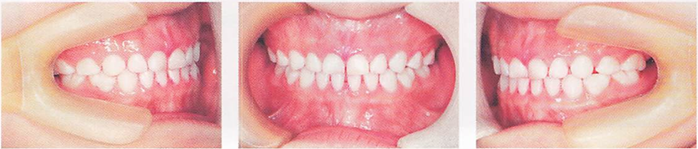

午後-91

8歳の女児。定期歯科健康診査で来院した。口腔内写真(別冊午後 No.36)を別に示す。 口腔内でみられるのはどれか。2つ選べ。

a.上唇小帯の異常

b.乳臼歯部の咬耗

c.前歯部の交叉咬合

d.Hellmanの歯齢ⅢB期

解答を見る

b.c